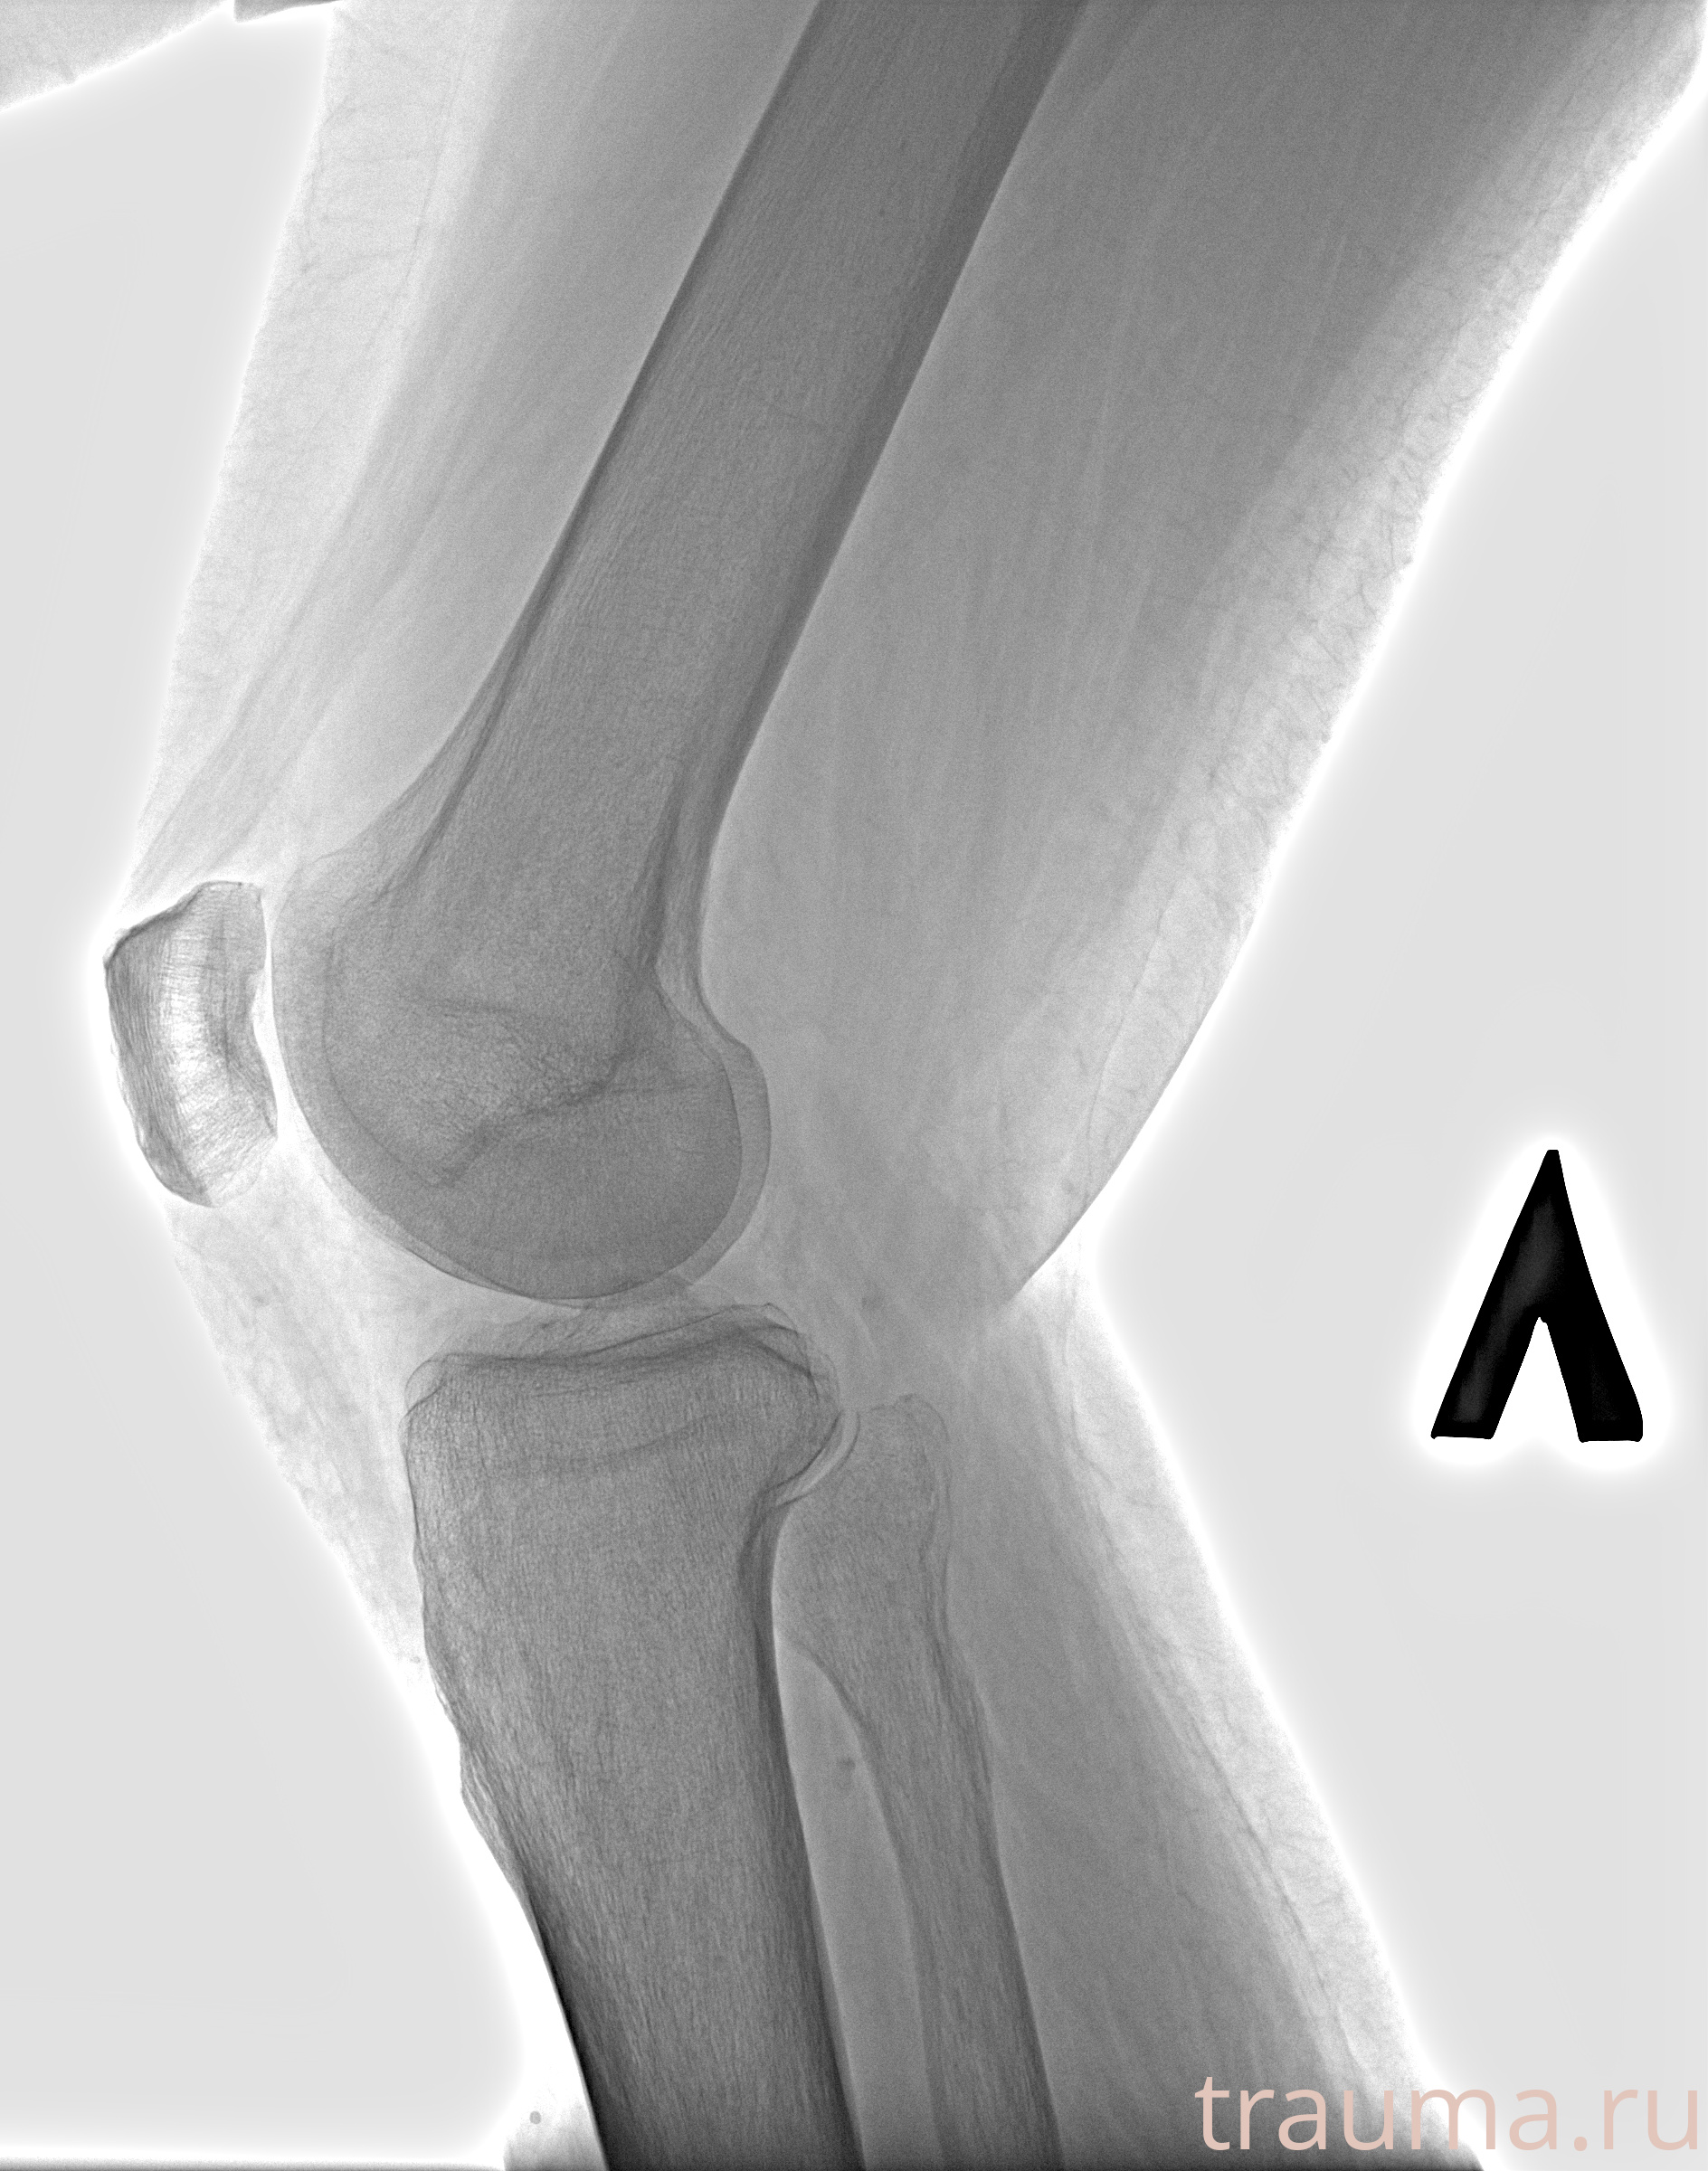

Рентгенограммы

Рентген на дому: по вашему адресу приезжает врач-рентгенолог, травматолог-ортопед с мобильным рентгеновским аппаратом, проводит диагностику травмы или заболевания, делает необходимые рентгенограммы, дает рекомендации по дальнейшему лечению. Получить качественные снимки в домашних условиях возможно благодаря уникальной методике, разработанной МосРентген Центром для института  Склифосовского